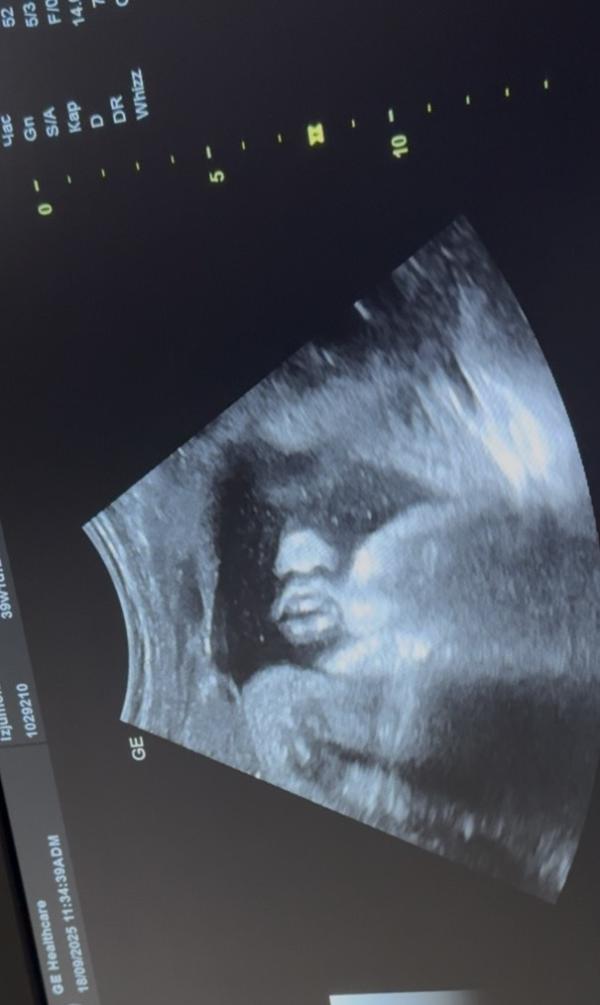

Какооой сладюююючий снимок получился, губки прелесть 😍😍🥰

ой какие губки бантиком🎀

это у мальчика или девочки такие будут?)